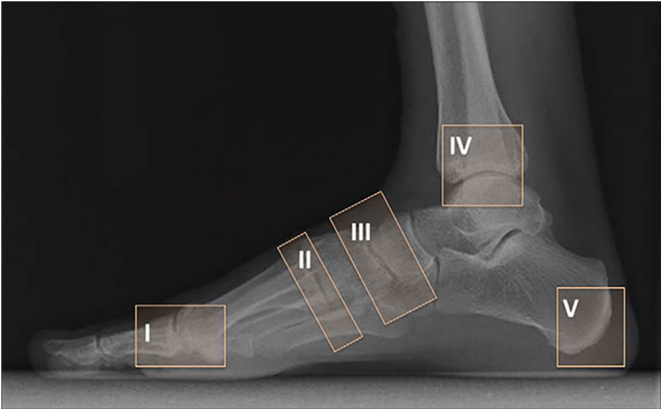

Charcot neuroarthropathy is the most severe complication of the diabetic foot. Its diagnosis is difficult and often overlooked, delaying management, with sometimes disastrous consequences. Its incidence is increasing due to the rapid global rise in the number of people with diabetes. Its pathophysiology remains unclear, although the activation of the RANK/RANK-L system appears to be involved, triggered either by neurotraumatic or neurovascular mechanisms, leading to the differentiation of monocytes into osteoclasts. Diagnosis relies on clinical and radiological arguments, particularly MRI. There are different types of Charcot foot depending on the evolution, according to Eichenholtz's classification and based on location according to Sanders and Brodsky's classifications. Treatment involves a multidisciplinary approach with diabetes management and addressing other general complications. Medical treatment is indicated as the first line, with offloading and immobilisation using a 'total contact cast'. In case of failure of this method, or if there is immediate deformity, surgical intervention is indicated, and techniques are evolving rapidly. Depending on the deformity, minimally invasive or arthroscopic procedures may be performed. In cases of significant deformity, foot reconstruction may be proposed, using the so-called 'super construct' technique if necessary. Infection will be treated concurrently or initially, depending on severity. Many complications are reported, but increasingly early and aggressive surgery improves patients' quality of life and reduces amputation rates.